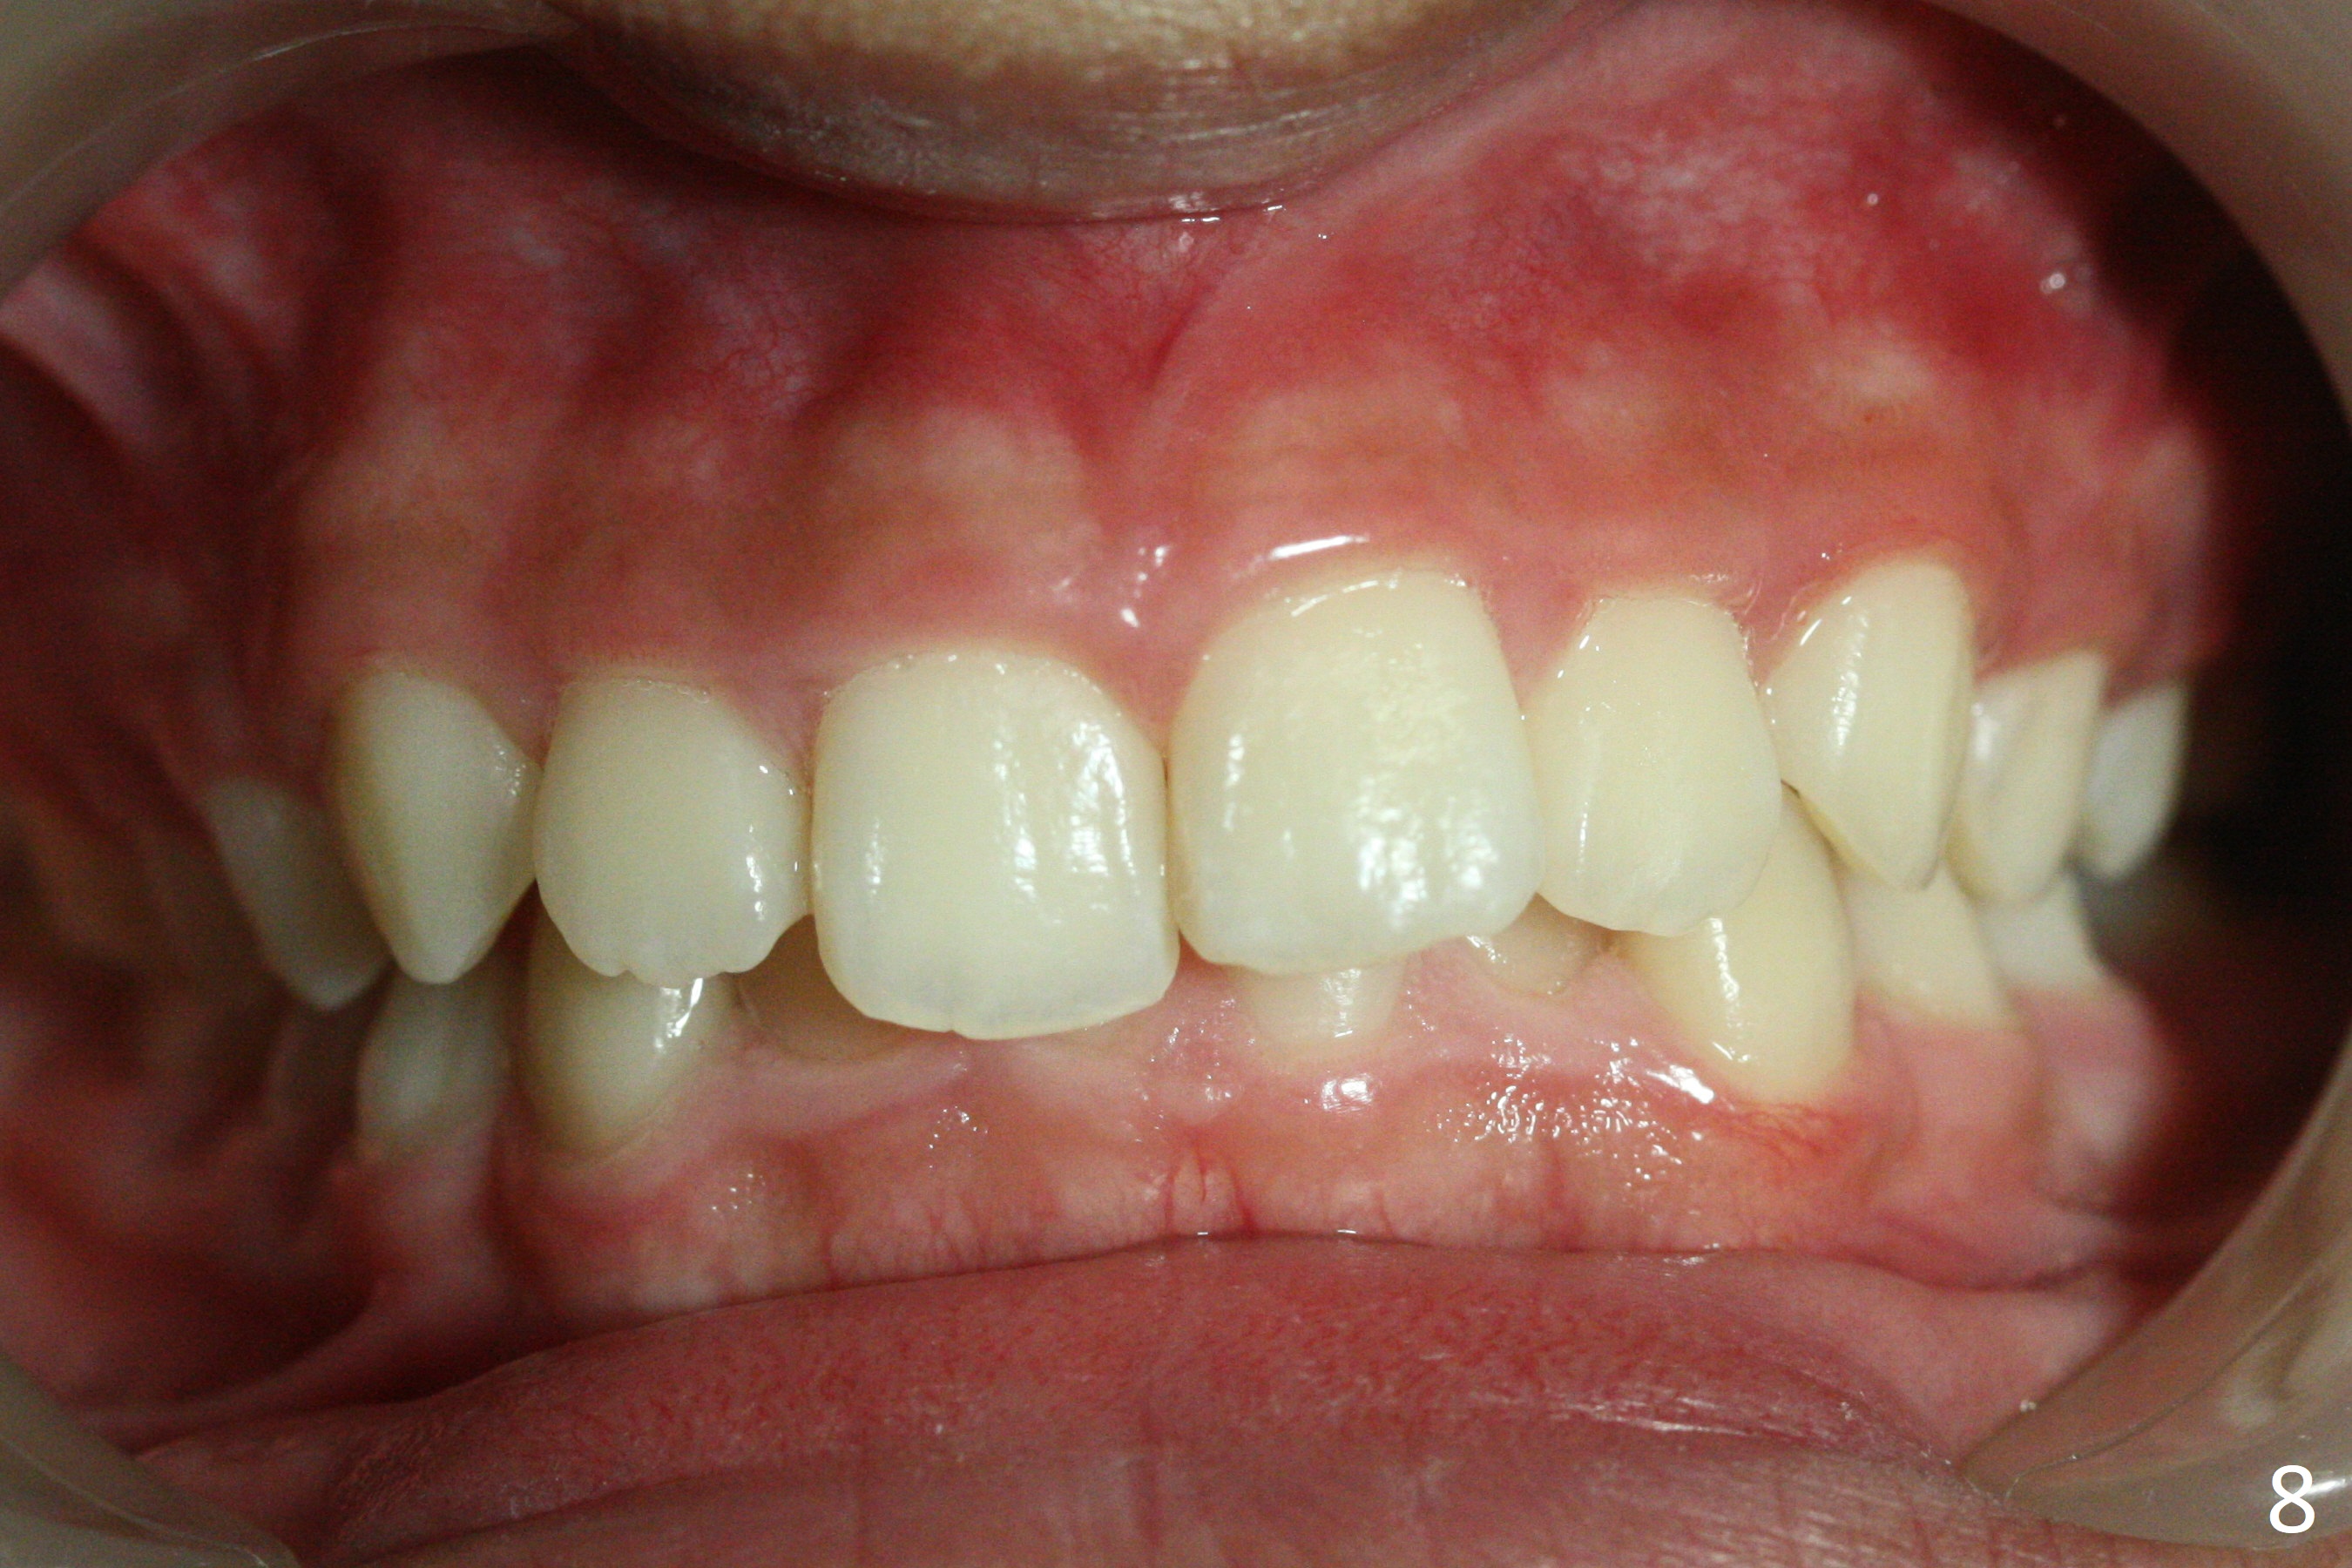

A 12-year-old woman has normal facial profile (Fig.1-6,12) and crowded dentition (7-11). Because of erupting 2nd molars (Fig.10,15), it is difficult to place rubber separators between U6/7. Copper ones are used instead (Fig.15 ^). Crowding and narrow arches (Fig.13,14) may be associated with the enlarged right Inferior Nasal Concha (Fig.15 *).